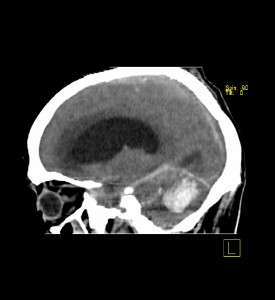

En la TC, la imagen característica de HIC es la presencia de una lesión de alta atenuación en relación con el parénquima cerebral circundante. Esta alta densidad está en relación lineal con el contenido proteico (hemoglobina) de la lesión hemorrágica y su apariencia radiológica variará con su tiempo de evolución. En una fase hiperaguda la colección está formada por plasma y células, y su apariencia en la TC es de una lesión heterogénea con una atenuación entre 30-60 UH, pudiendo resultar difícil distinguirla del cerebro normal. En los siguientes minutos u horas se forma un coágulo de fibrina, que progresivamente se retrae, expulsando el suero, aumentando su atenuación hasta las 80-100 UH, esta sería la fase en la que se encuentra el paciente que nos ocupa. Debemos tener en cuenta que estas características pueden perderse en casos de anemia grave o coagulopatías que impidan o dificulten la formación de un coágulo, pero no es el caso. En los días sucesivos se produce una progresiva lisis proteica y celular que conduce a una disminución de la atenuación que se inicia en la periferia y se extiende hacia el centro de la lesión. Entre los días 4 y 9 su atenuación es similar a la de la sustancia gris y hacia la segunda o tercera semana es similar a la de la sustancia blanca. Finalmente, puede desaparecer entre los 2 y 6 meses, o permanecer como una hendidura o experimentar una calcificación.

Podemos ver en la imagen además, que el cuarto ventrículo está colapsado por el efecto masa creado por la hemorragia.